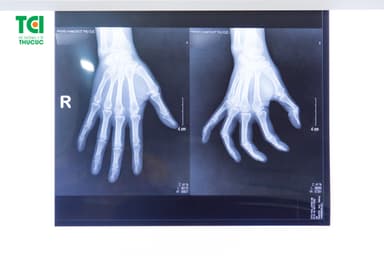

3 điều cần biết về bệnh viêm khớp ngón tay

Viêm khớp ngón tay là căn bệnh thường gặp ở đối tượng người cao tuổi. Bệnh gây nên việc hạn chế sự cử động khớp ngón tay cái và làm ảnh hưởng đến hoạt động sinh hoạt hàng ngày. Vì vậy, việc chẩn đoán và điều trị sớm có thể giúp làm bệnh nhân giảm triệu chứng, cử động ngón tay linh hoạt hơn.